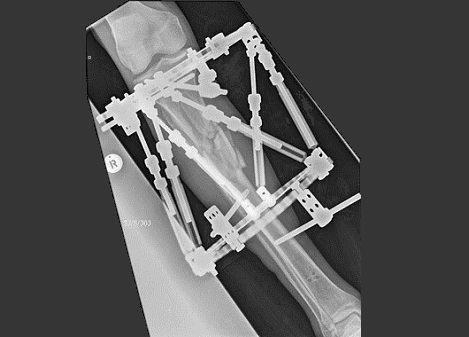

Fig7. - Complex proximal tibia fracture.

Fig7. - Treated with a hexapod type external fixator.